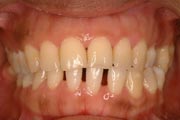

Crowding

Before